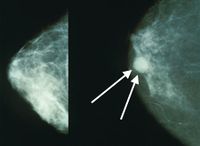

سرطان الثدي

مقالة مفصلة: سرطان الثدي

| سرطان الثدي | ||

| معدل الانتشار | 2.1 مليون (2015) | |

| معدل البقاء 5 سنوات | ~85% (الولايات المتحدة والمملكة المتحدة)[4] [5] | |

| حالات الوفاة | 533.600 (2015)[6] | |

| عوامل الخطورة | طفرات موروثة في الجين BRCA1 أو الجين BRCA2؛ تقدم العمر؛ البدء المبكر للحيض؛ تأخر الإياس (سن اليأس)، عدم إنجاب أي طفل أو إنجاب الطفل الأول بعد سن الثلاثين؛ التاريخ الشخصي personal history أو العائلي للإصابة بسرطان الثدي؛ وربما يكون للغذاء الغني بالدهون دور في ذلك. تنخفض معدلات الوفيات بين النساء البيض ولا سيما اللواتي تقل أعمارهن عن الخامسة والستين. | |

| العلامات المنذرة | وجود كتلة غير مؤلمة في الثدي هو علامة نموذجية، وقد تكون مؤلمة أحيانا؛ أي تغير في لون أو شكل أو طبيعة نسيج الثدي أو الحلمة؛ إفراز discharge من الحلمة أو التألم عند جَسِّها. | |

| الكشف والتشخيص | الفحص الذاتي والفحوص السريرية للثدي، تصوير الثدي الشعاعي mammogram. ينصح الخبراء أن يُجرى سنويا تصوير شعاعي وفحص عام للثدي لجميع النساء اللواتي تتجاوز أعمارهن الخمسين، بل ولبعض النساء الأصغر أيضاً.

| |

| العلاج | يمكن أن يكون الاستئصال الكامل للثدي mastectomy مناسبا للأورام الموضّعة. وقد يفضل في كثير من الأحيان الجراحة المحافظة على الثدي breast-conserving surgery (بإزالة الورم وبعض النسج المحيطة به وتسمى أحياناً استئصال الكتلة lumpectomy) متبوعة بمعالجة شعاعية موضعية. وعلى الرغم من أن نسبة المعاودة (الانتكاس) أكبر في الجراحة المحافظة على الثدي، فإن هذه المعاودات يمكن علاجها باستئصال الثدي كاملا. وعلى كل حال، فإن نسبة البُقيا في هذه الحالة مساوية للحالات التي تعالج باستئصال الثدي في البداية. وقد يُتبع كل من الإجراءين بمعالجة كيميائية إضافية أو بمعالجة حاصرة للهرمونات. وإذا كانت الخلايا الورمية تحوي مستويات عالية من مستقبلات هرمونات الإستروجين والپروجسترون فإن هذا مؤشر جيد، إذ تستطيع المعالجة الحاصرة للهرمونات إيقاف نمو هذه الخلايا.

| ملاحظات | آراء خلافية: على الرغم من أن الفحوص التي تُجرى للكشف عن الطفرات الوراثية في الجينيْن BRCA1 و BRCA2 قد صارت متوافرة، فإن الأطباء لم يصلوا إلى إجماع على استخدام هذه الفحوص. كما أن جدوى إجراء المعالجة الكيميائية عند المريضات المسنّات وجدوى تصوير الثدي الشعاعي الروتيني لمن لم يَبْلغن سن الخمسين، ما زالتا موضع جدل. وتشير بعض الدراسات إلى أن المعالجة الجراحية لسرطان الثدي خلال النصف الثاني من الدورة الطمثية للمريضة قد تعطي نتائج أفضل. | |